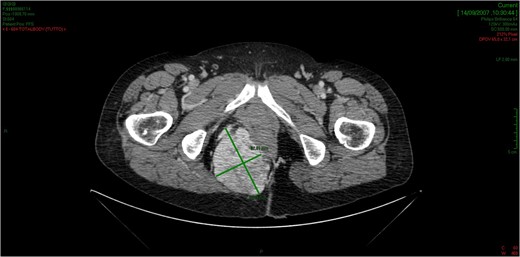

CT showed an hyperintense and inhomogeneous solid lesion taking up the right ischiorectal fossa (maximum diameter of about 10 cm), extended cranially until impressing the wall of the rectal ampulla, with no apparent infiltration (Figs 2 and 3). The lesion presented an intense contrast enhancement, sign of a rich vascularization (Fig. 4).

The tridimensional reconstruction shows the rich vascularization of the neoplasm.